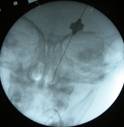

| Lacrimal probing sequence. Fluoroscopy showing the position of the probe | ||

This technique is very quick and can take less than one minute.

Afterwards we verify successful opening of the pathway by irrigation and checking its output in the nostril or endoscopically.